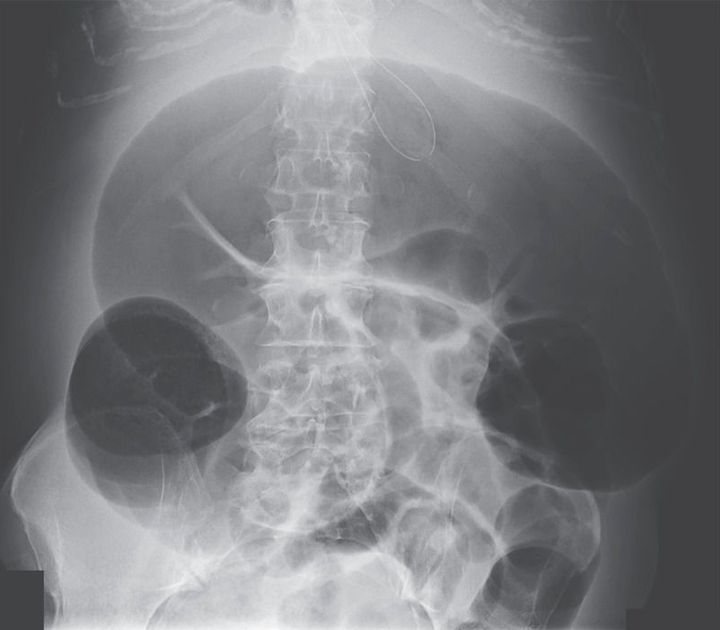

A 70-year-old woman with end-stage liver disease from hepatitis C was admitted to the hospital for confusion. Portosystemic encephalopathy was diagnosed, and the patient was treated with 20 g of lactulose every 6 hours. A few days after admission, abdominal pain with marked abdominal distention developed. There was no fever or leukocytosis. Abdominal radiography showed a distended, air-filled colon to the level of the splenic flexure, with the cecum and transverse colon measuring 11 cm and 14 cm, respectively. Subsequent abdominal computed tomography showed marked distention of the proximal colon with an abrupt transition to a decompressed colon at the level of the proximal descending colon, with no evidence of an obstructing lesion. A diagnosis of acute colonic pseudo-obstruction, or Ogilvie's syndrome, was made. She was initially treated conservatively with the administration of intravenous fluids and the use of nasogastric and rectal tubes. The use of neostigmine was contraindicated, given the acute renal failure. When her abdominal discomfort worsened, colonoscopic decompression was performed, resulting in marked improvement. Acute colonic pseudo-obstruction is characterized by massively dilated large-bowel segments in the absence of mechanical obstruction and can be seen in a wide variety of medical and surgical illnesses.